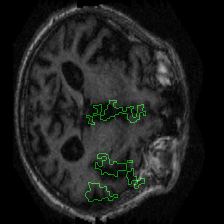

Figure 1 presents attribution maps generated using PWIG for a selection of MRI scans across all four diagnostic categories. The highlighted regions (in green) correspond to the areas that contributed most significantly to the model’s decision. Notably, we observe consistent emphasis on anatomical structures that align with clinical markers of dementia, including cortical and subcortical regions. For instance, in the moderate and mild dementia examples, the model focuses on regions exhibiting visible atrophy or abnormal morphology. In contrast, attribution maps for non-demented subjects appear more diffuse and less concentrated, reflecting the model’s detection of normal anatomical patterns.

The results in Figure 1 demonstrate that PWIG can effectively produce interpretable and clinically meaningful explanations for model predictions in medical imaging tasks.

Figure 1: PWIG attribution maps across dementia categories using the OASIS-1 dataset. Green overlays indicate regions with the highest attribution scores.